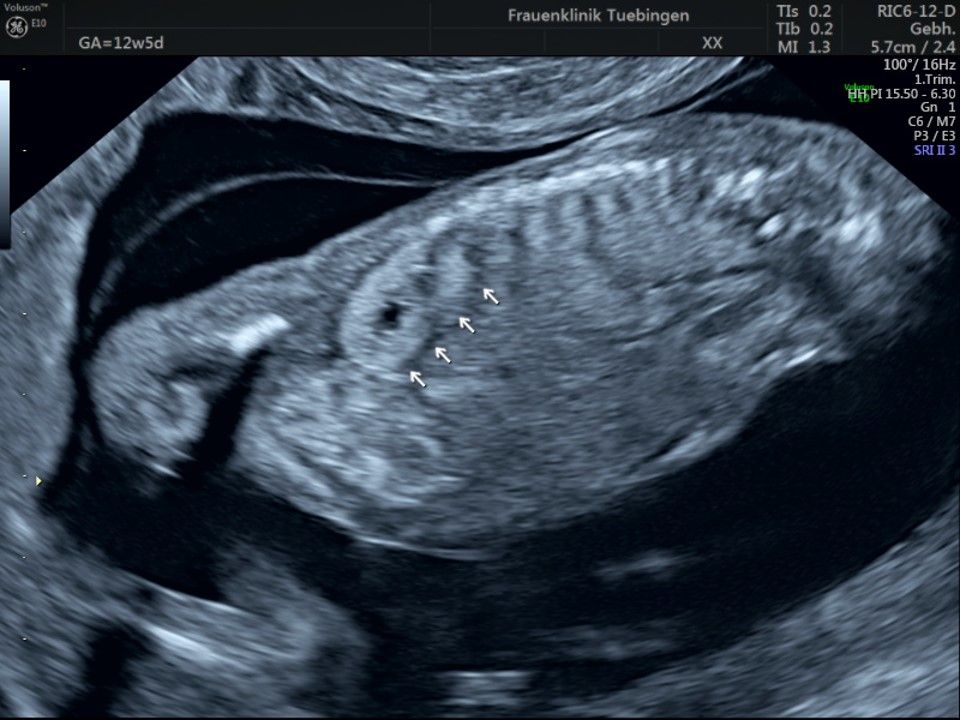

Das Ergebnis der Ultraschalluntersuchung ist wegweisend. Dabei wird der Fet vermessen, die Organe werden untersucht und die sonographischen Marker zur Risikoberechnung für Chromosomenstörungen werden beurteilt. Das sind: die Nackentransparenzdicke, Nasenbein sowie der Blutfluss in der rechten Herzhälfte und im Ductus venosus, einem Gefäß in der Leber des Feten.

Findet sich eine Fehlbildung oder ist die Nackentransparenzdicke deutlich erhöht, werden wir mit Ihnen eine Abklärung mittels Fruchtwasser- oder Mutterkuchenpunktion besprechen. Ob diese dann tatsächlich durchgeführt wird, müssen wir in einem gemeinsamen Gespräch klären.